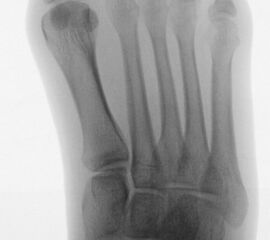

Abb. 2 a-c: offene Wachstumsfugen MT I Basis und Zehen (a), teilweise geöffnete Wachstumsfugen (b) und geschlossene Wachstumsfugen (c).

Zum Lesen der Bildbeschreibung und zur Vollansicht bitte die Bilder anklicken. Bilder: A. Helmers.